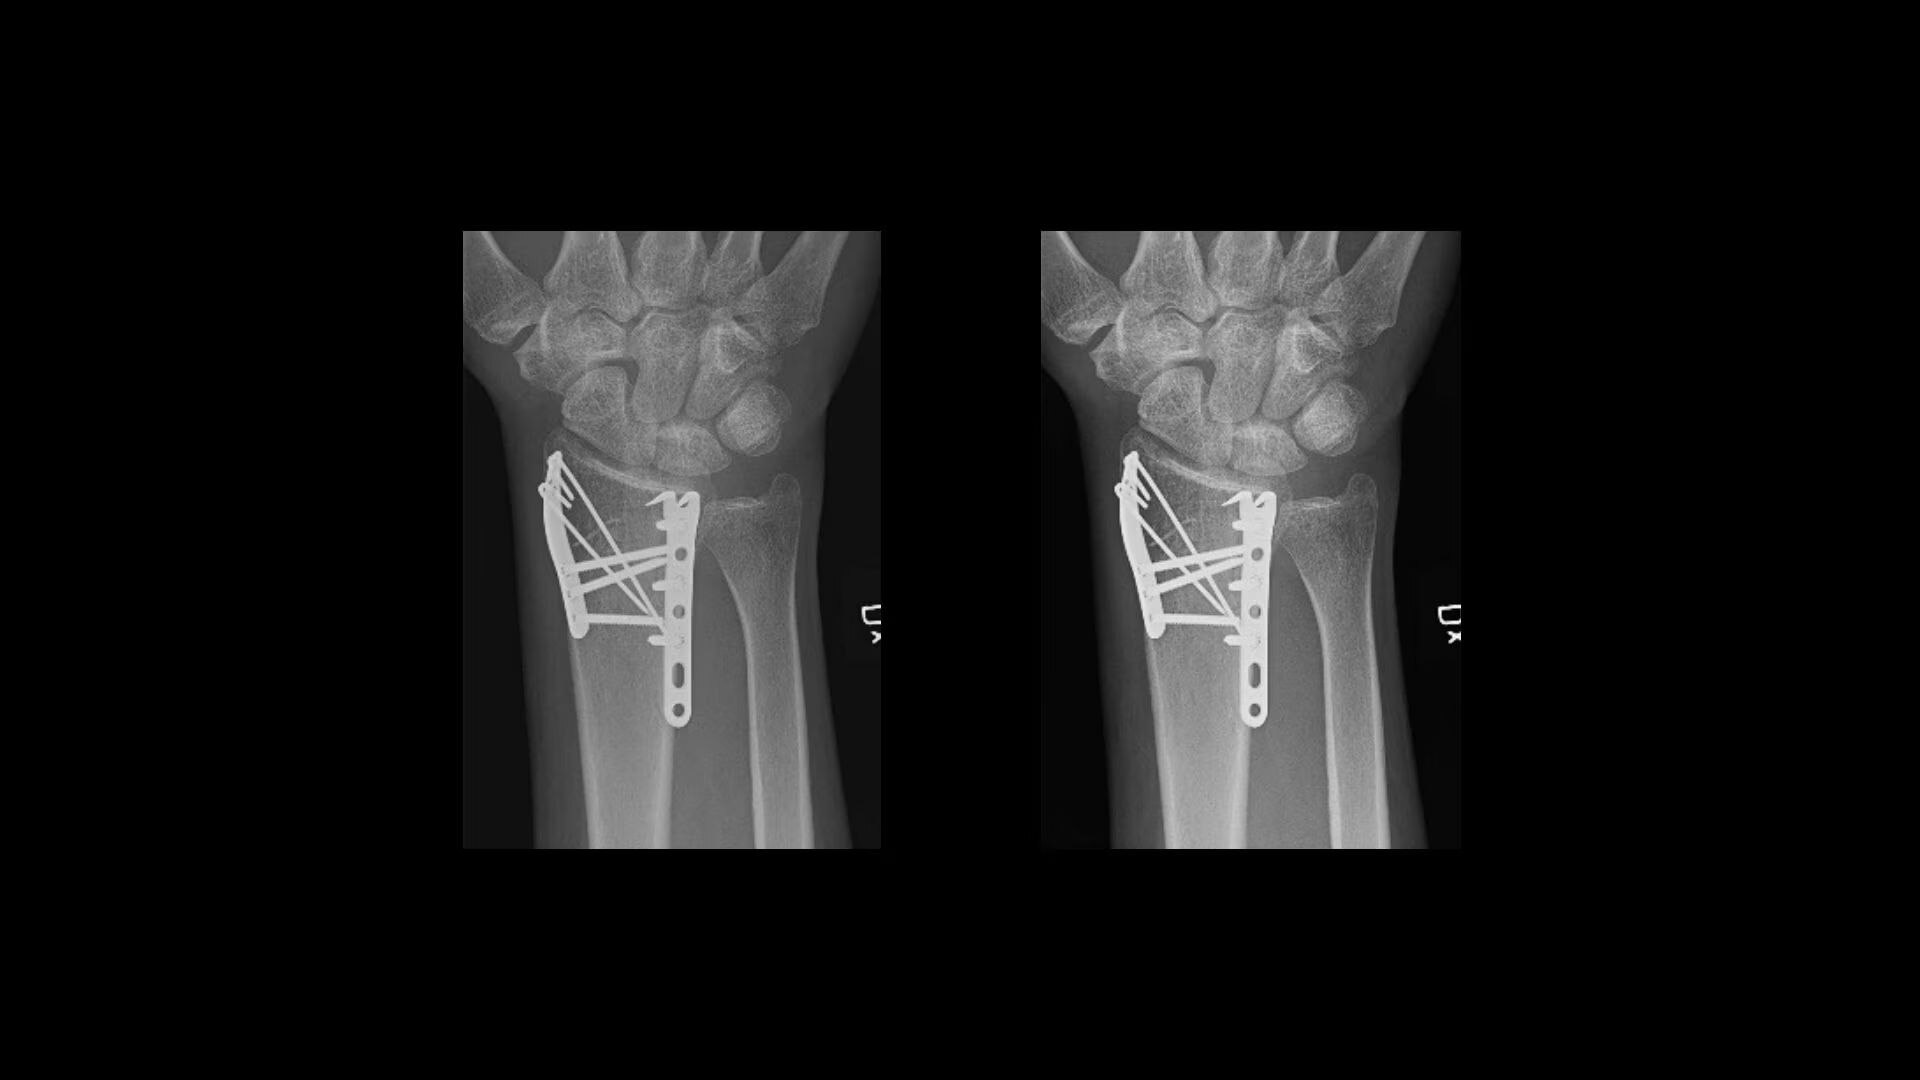

Metal implant handling

See clear bone-metal interface without halo artifact

Flexibility

Reach a diagnosis, quickly

Helix offers four predefined sets of anatomy- and view-specific “looks” for different levels of contrast, brightness, edge enhancement, noise reduction and tissue equalization.

Real-time IP Looks provides faster and easier fine-tuned customizations.

IQ Compare allows for simultaneous viewing of standard and customized looks to simplify comparisons.

QuickEnhance offers one-touch reprocessing of images with a custom look. It is customizable by anatomy for multiple uses, including instrument check, implant visualisation and line placement.